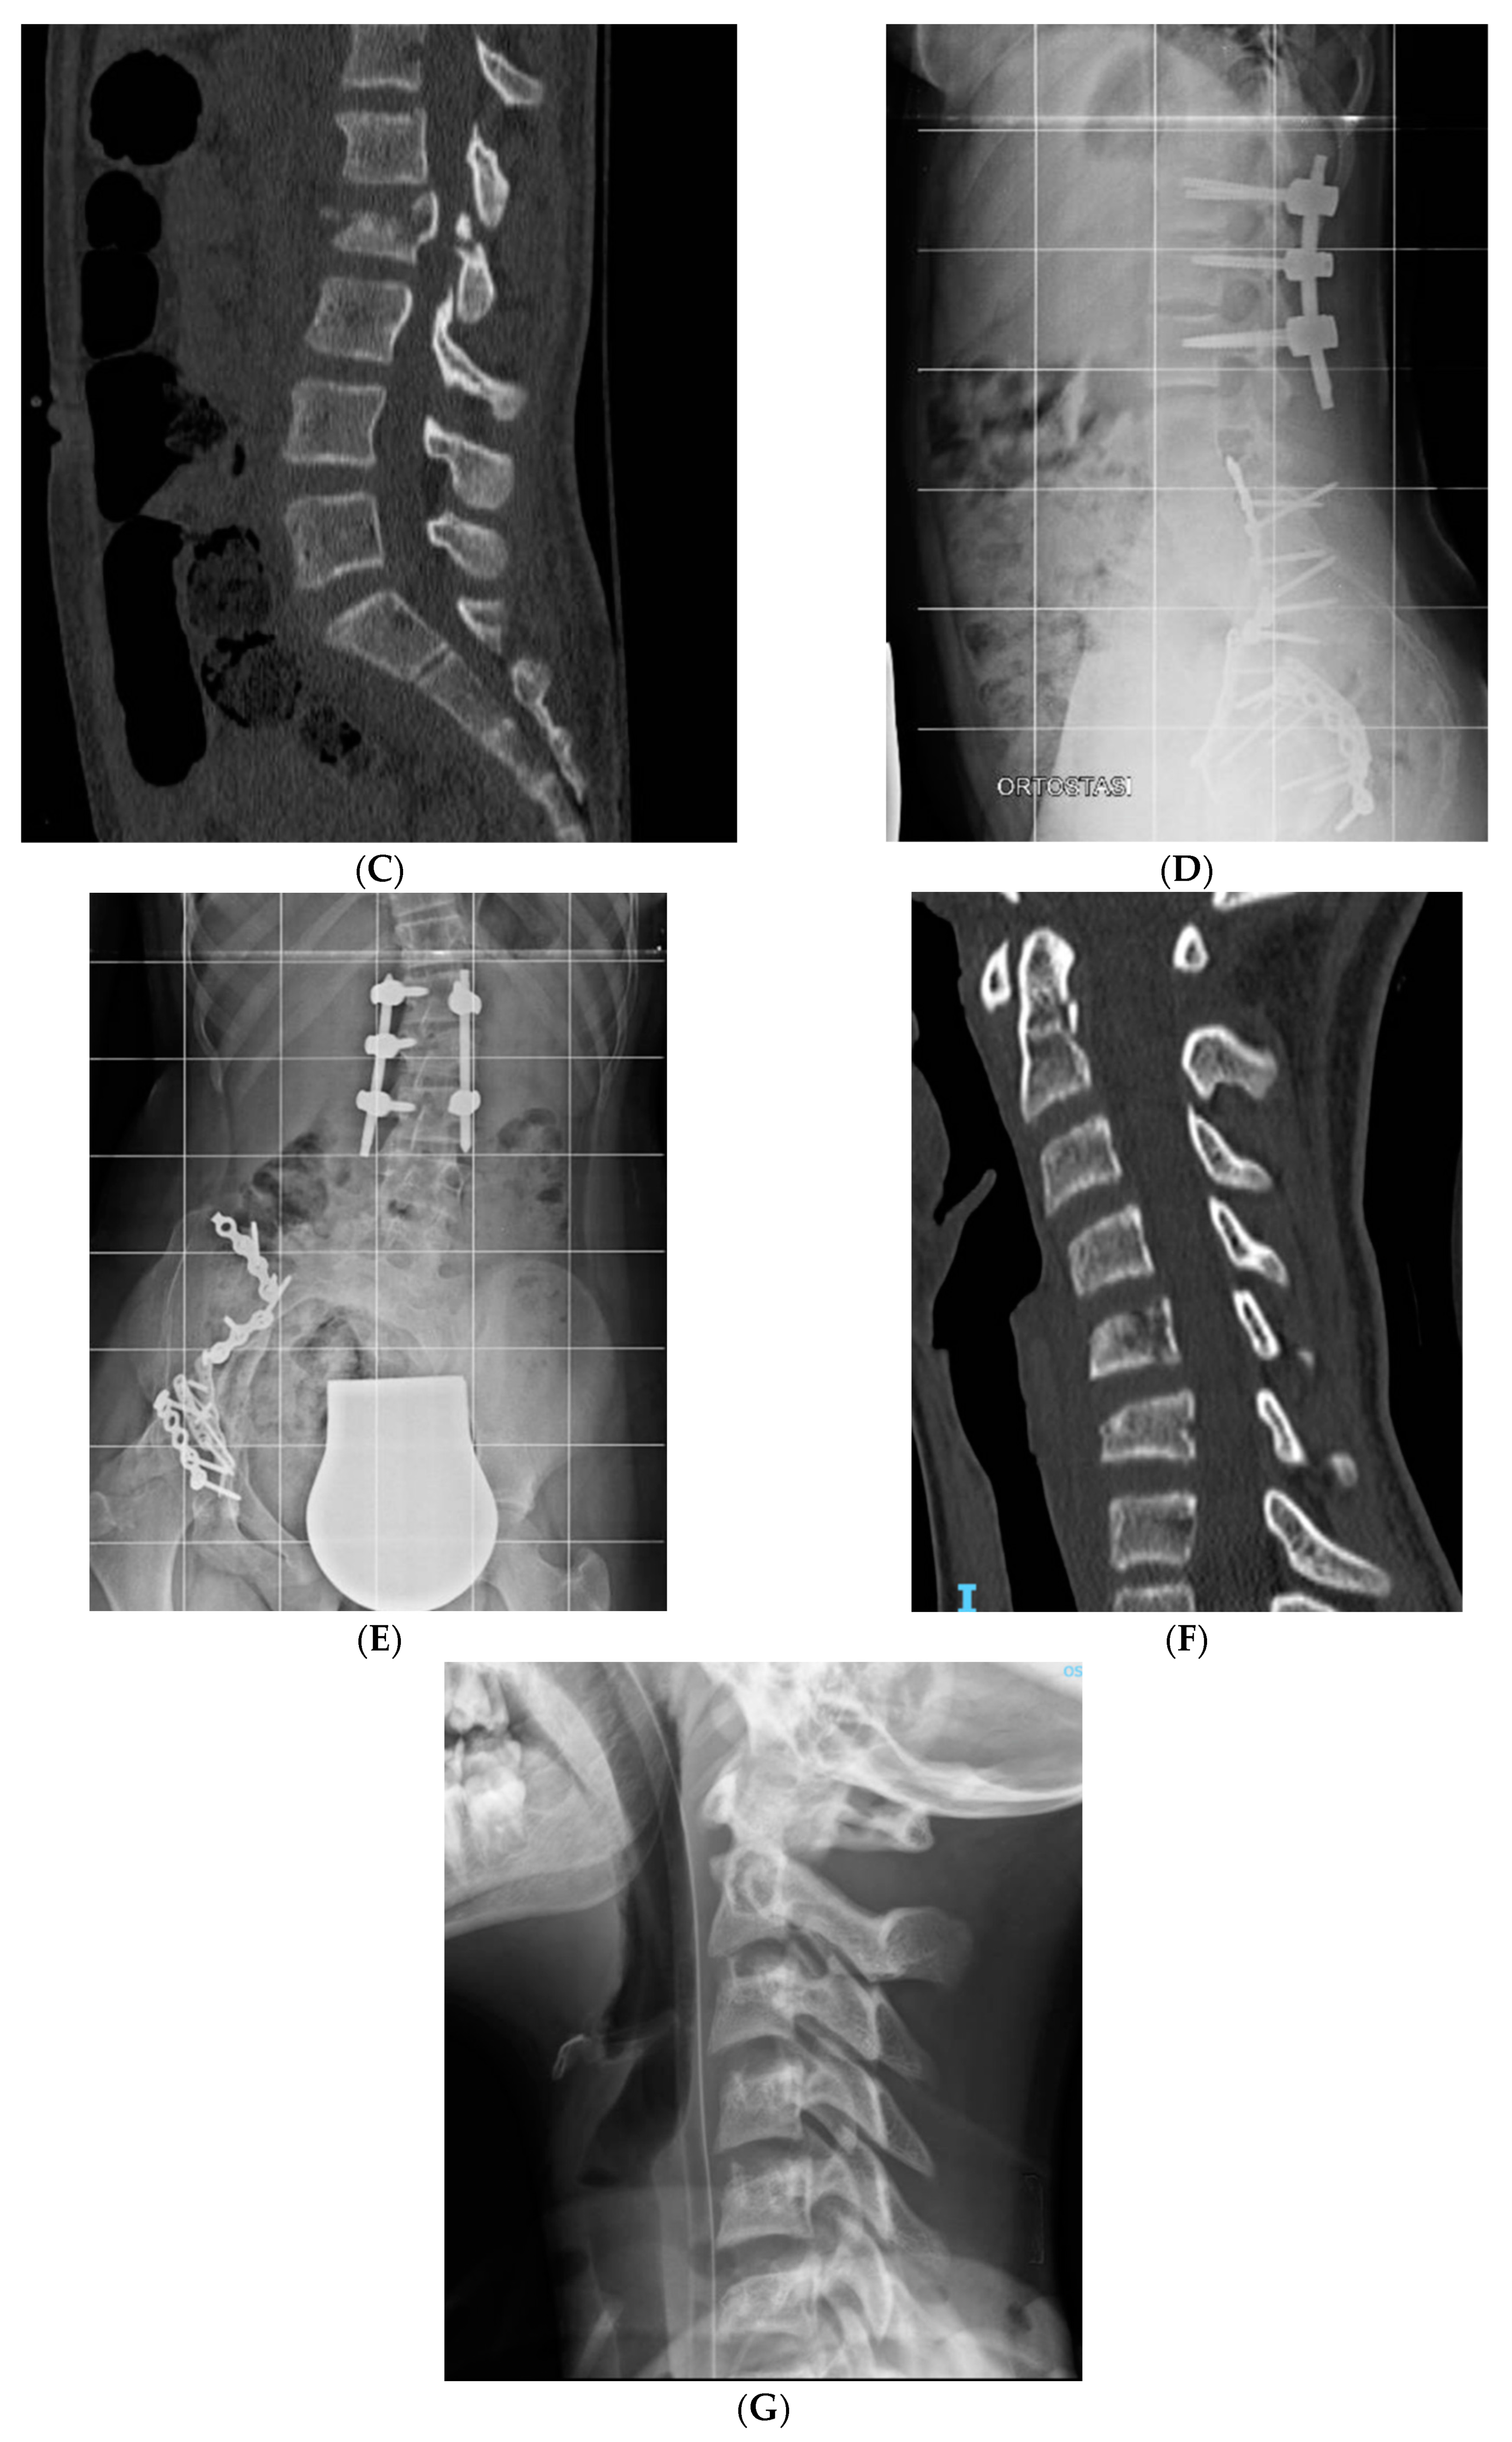

Only two patients with thoracolumbar A0 and A1 types of fractures (cases 4 and 5, Table 1) were conservatively treated with a rigid thoracolumbar orthosis for 3 months with good compliance and results. Percutaneous pedicle fixation was applied in seven patients with an indirect decompression and to restore a better sagittal balance (images case 6 and 10, Table 1). Only in two cases there were a neurological impairment. In both cases an open spinal decompression and posterior spinal fusion was performed open. All surgically treated patients used a soft spine orthosis for 1 month to facilitate early mobilization and to reduce muscular pain.

Figure 1. Case 6 (Table 1), (A,B) preoperative axial CT scan of L1 and L2, (C) preoperative sagittal CT scan of lumbar spine, (D,E) anteroposterior and lateral Xray of lumbar spine after surgery, (F) Sagittal CT scan of post traumatic cervical spine, (G) Xray lateral view in Halo-Vest.